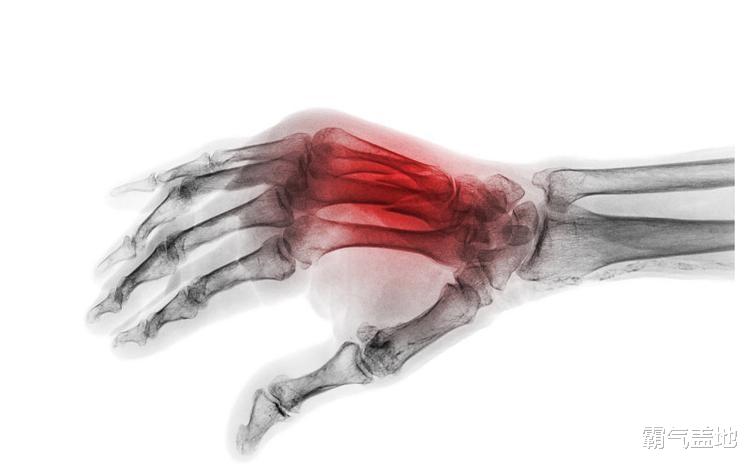

最简单的方法,就是摸摸孩子的手指。 如果你发现孩子的手指骨骼摸起来完全“硬邦邦”的,关节附近也摸不到软骨的那种感觉,那可就要注意了,这很可能暗示着骨骺线即将闭合。或者,你可以观察孩子手指的长度,如果好几年都没有明显变化,也要警惕起来。